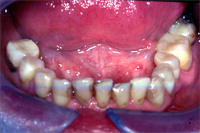

Die Situation eines 67 Jahre alten Patienten, dem ich im Verlaufe einer Zahnsanierung alle alten Amalgamfüllungen (s. Amalgamersatz) im Unterkiefer durch Komposite ersetzte, ist in den Abb. 1 vor und in Abb. 2 nach der Behandlung zu sehen. Möglich war dies nur dank der Full Bond Technik.